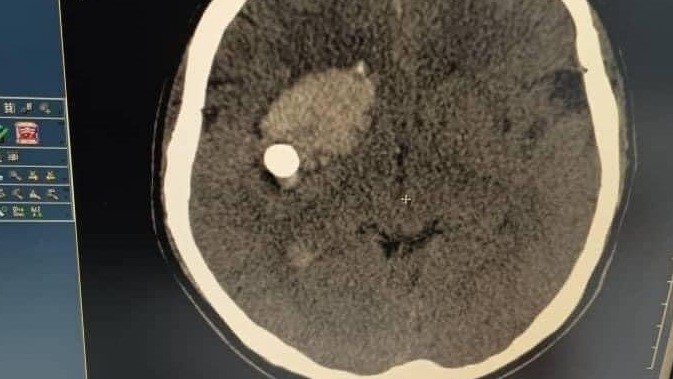

Семилетний ребенок выстрелил из тира в своего брата в возрасте 7 месяцев — пуля застряла в черепе